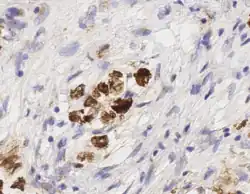

Ki67 stain calculation by QuPath in a pure seminoma, which gives a measure of the proliferation rate of the tumor. The colors represent the intensity of expression: blue-no expression, yellow-low, orange-moderate, and red-high expression.[14] -

_stain_of_mixed_malignant_germ_cell_tumor_-_crop.png)

Digital pathology has been approved by the FDA for primary diagnosis.[16] The approval was based on a multi-center study of 1,992 cases in which whole-slide imaging (WSI) was shown to be non-inferior to microscopy across a wide range of surgical pathology specimens, sample types and stains.[17] While there are advantages to WSI when creating digital data from glass slides, when it comes to real-time telepathology applications, WSI is not a strong choice for discussion and collaboration between multiple remote pathologists.[18] Furthermore, unlike digital radiology where the elimination of film made return on investment (ROI) clear, the ROI on digital pathology equipment is less obvious. The strongest ROI justification includes improved quality of healthcare, increased efficiency for pathologists, and reduced costs in handling glass slides.[19]